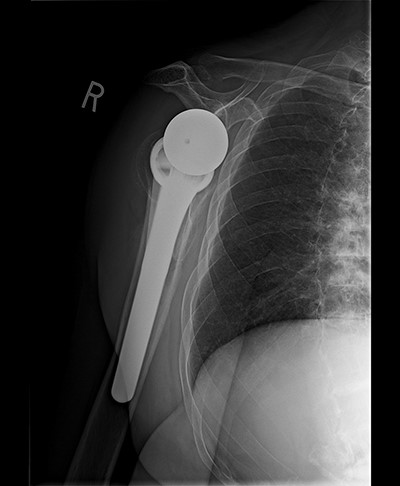

Radiologic imaging revealed bone-on-bone apposition of the glenohumeral joint, with superior humeral head migration consistent with rotator cuff tear arthropathy (Figs 1 and 2).

Standard metaglene was positioned superiorly within the glenoid fossa to accommodate a 145° epiphysis and +4-mm lateralized glenosphere (Figs 4 and 5). There were no intraoperative complications.